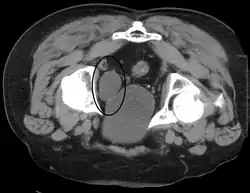

Investigations performed usually include collecting a sample of urine for an inspection for malignant cells under a microscope, called cytology, as well as medical imaging by a CT urogram or ultrasound.[33] If a concerning lesion is seen, a flexible camera may be inserted into the bladder, called cystoscopy, in order to view the lesion and take a biopsy, and a CT scan will be performed of other body parts (a CT scan of the chest, abdomen and pelvis) to look for additional metastatic lesions.[33]

Some forms of medical imaging exist to visualise the bladder. A bladder ultrasound may be conducted to view how much urine is within the bladder, indicating urinary retention. A urinary tract ultrasound, conducted by a more trained operator, may be conducted to view whether there are stones, tumours or sites of obstruction within the bladder and urinary tract. A CT scan may also be ordered.